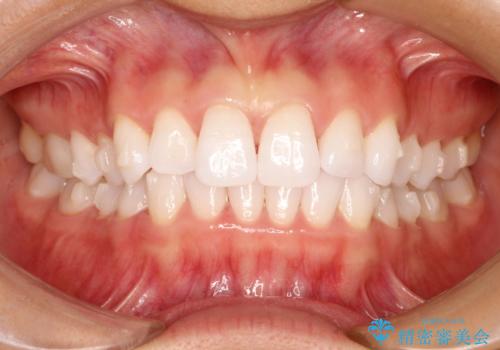

気になる前歯の歯並びをインビザラインで矯正

- 前歯の傾きと、ガタガタが気になるとのことで来院されました。

アスリートの方でしたので、競技に支障が少ないインビザラインで治療することとなりました。

前歯の傾きや高さをシミュレーションで患者様と確認しながら、歯並びを仕上げていきました。